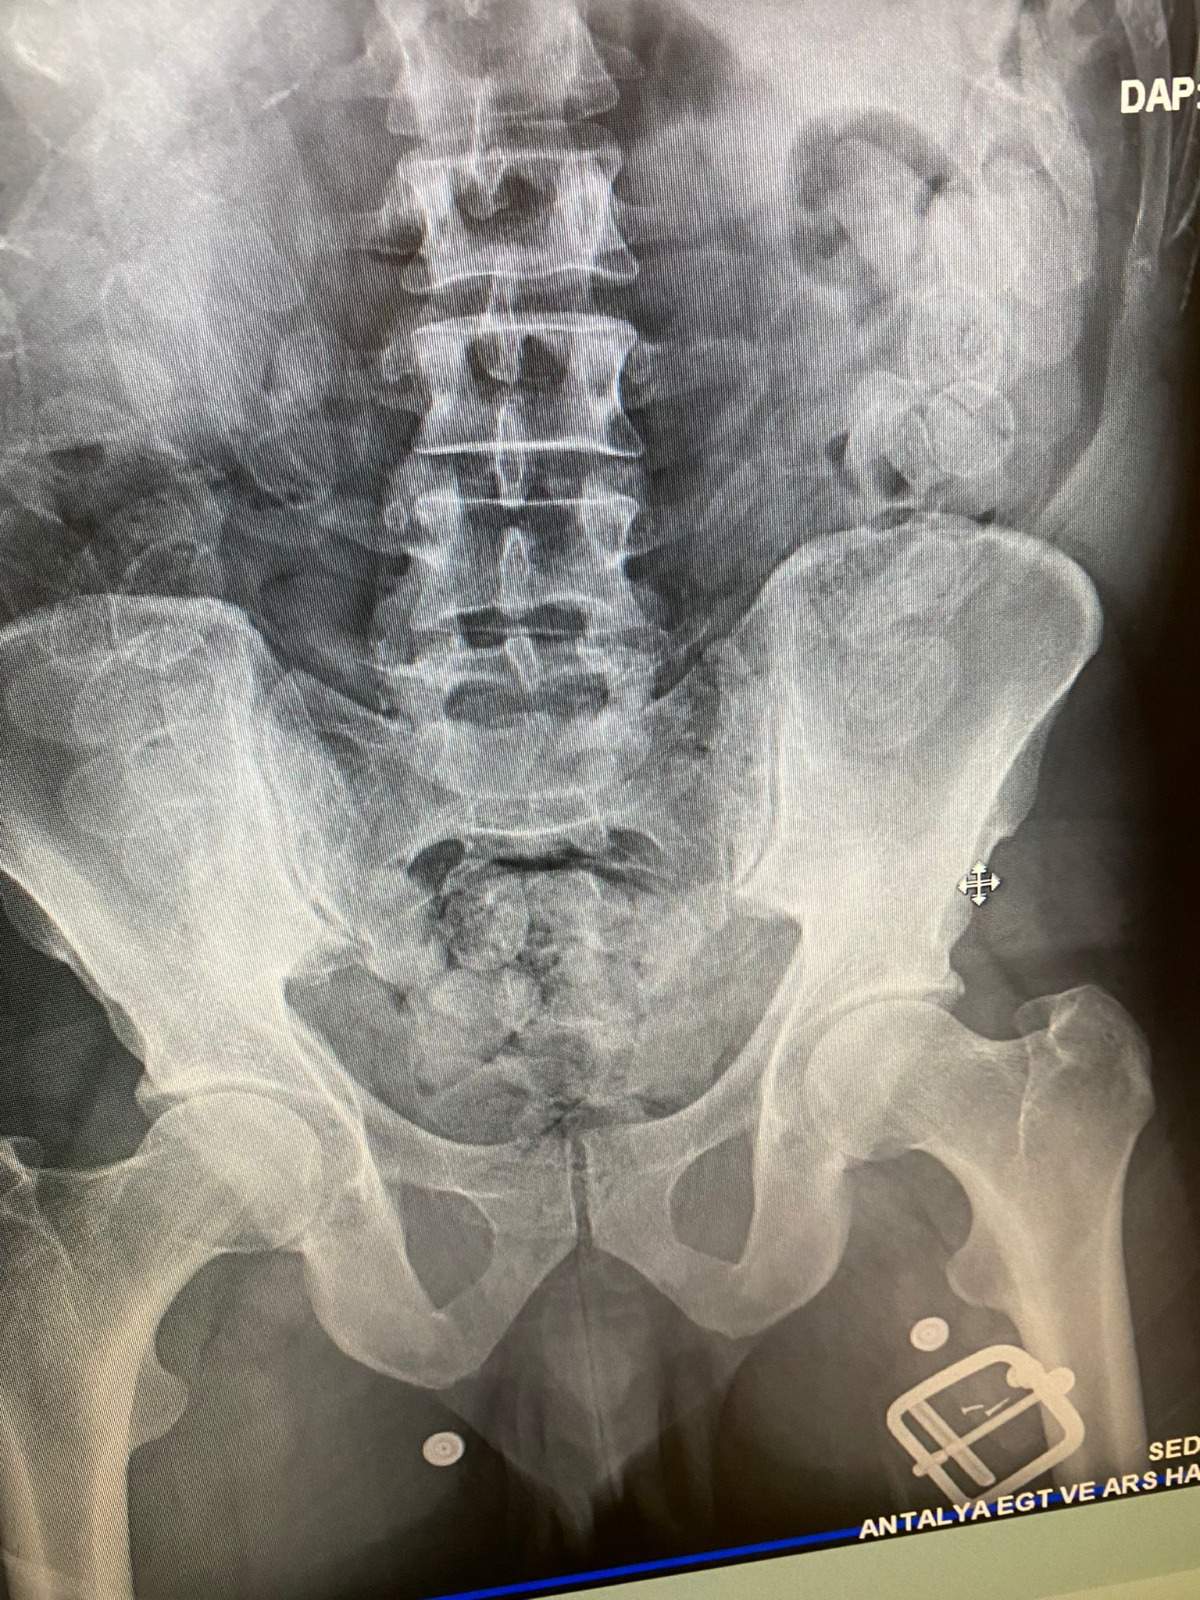

Antalya Havalimanı'na gelen Fas uyruklu H.L.'nin şüpheli tavırlar sergilemesi üzerine Narkotik Suçlarla Mücadele Şube Müdürlüğü Hudut Kapıları Büro Amirliği ekiplerince yaptırılan iç beden muayenesinde 100 adet kapsül halinde daralı 1100 gram macun esrar maddesi yakalandı. Gözaltına alınan şüpheli H.L. hakkında “Uyuşturucu veya Uyarıcı Madde Ticareti Yapma veya Sağlama” suçlarından işlem yapıldı.